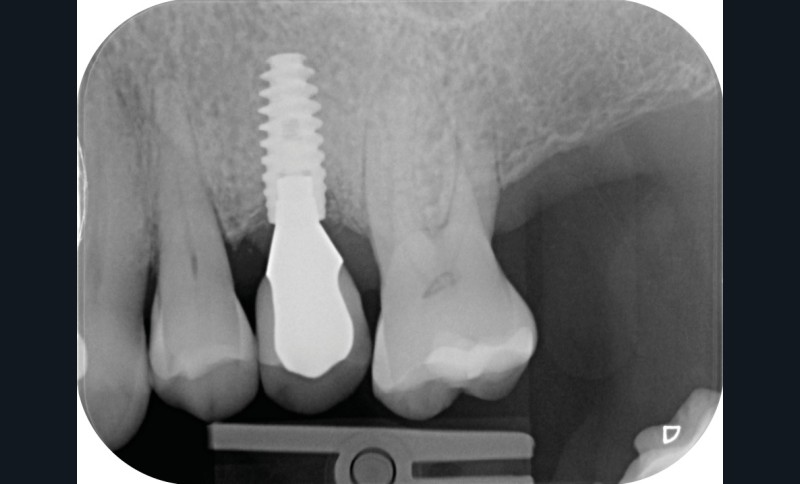

Chez cette patiente, le traitement de la péri-implantite a été réalisé à l’aide d’une technique de régénération osseuse guidée péri-implantaire, dont l’indication a été principalement motivée par la morphologie du défaut osseux. Au-delà de la maîtrise du geste chirurgical, le bon résultat obtenu à trois ans est intimement lié à sa coopération en termes de suivi et de contrôle de plaque.

13 et 14. À 3 ans, une régénération osseuse satisfaisante et un bel aspect des tissus péri-implantaires sont observés. Les poches font 3 mm en mésial, distal et palatin, et 2 mm en vestibulaire. Il n’y a pas de saignement au sondage.